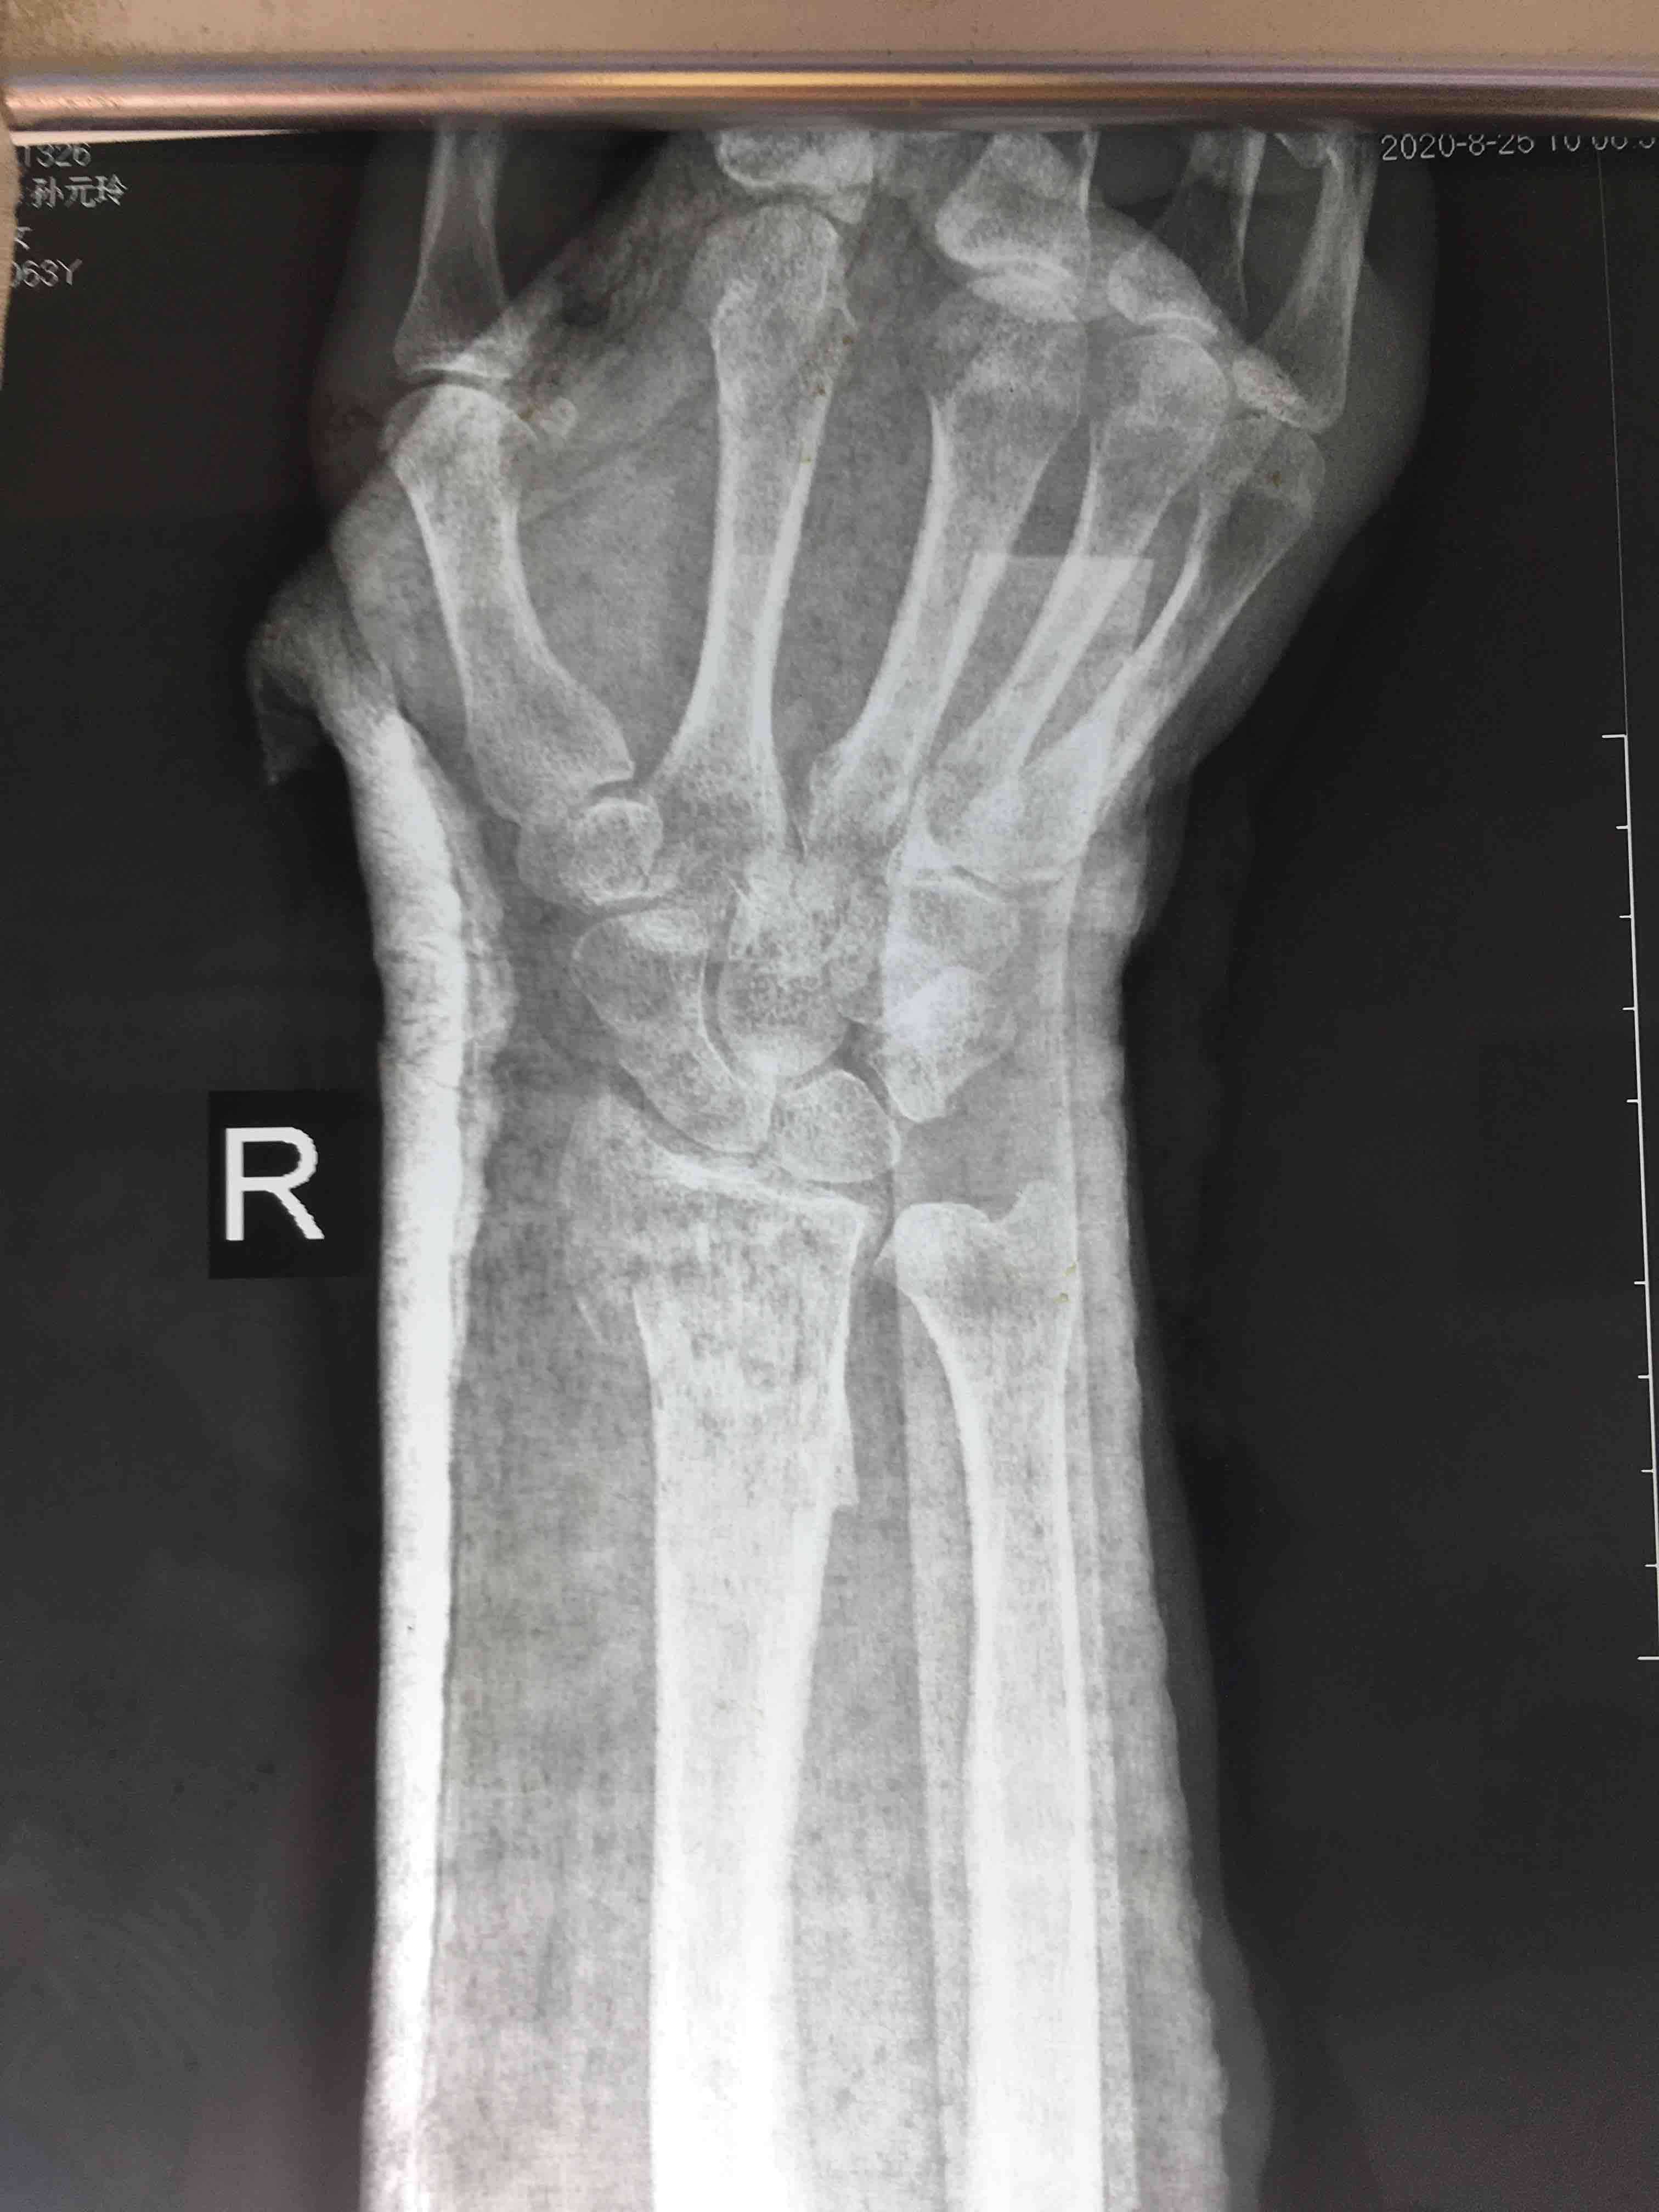

斯密斯骨折(保守治疗失败一例)

摔伤后右腕肿痛,畸形1小时入院。既往身体健康,无特殊不良嗜好。

右腕部肿胀明显,畸形,局部皮色皮温正常,压痛及纵向叩击痛阳性,活动受限,末梢血运感觉正常。

切开复位内固定术,术后抗炎,消肿等处理。